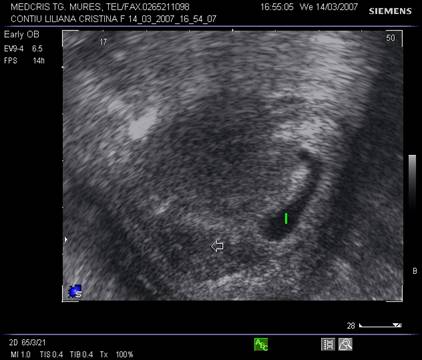

8.Sarcina si dispozitivul intrauterin

Pacienta purtatoare de IUD va fi examinata pentru a stabili locul dispozitivului in cavitatea uterina. Daca acesta a fost evacuat sarcina va continua fara risc. Daca IUD este inca intracavitar, va trebui decis daca trebuie extras in functie de pozitie si de varsta sarcinii.

Ecografic, dispozitivul apare ca o structura ecogena cu forma variabila, localizat alaturi deasupra sau sub sacul gestational, eventual in canalul cervical.

Daca dispozitivul intrauterin prin pozitia sa nu poate fi extras, continuarea sarcinii poate fi grevata de cresterea riscului de avort, infectii, perforatii, nasteri premature. Prezenta asocierii IUD cu sarcina nu constituie indicatie de avort si nu creste riscul de anomalii fetale.

La pacientele cu teste pozitive si IUD prezent se va cerceta cu grija regiunea anexiala bilateral pentru a exclude o sarcina ectopica.

Fig nr. 90. Dispozitiv intrauterin dislocat in col, la o sarcina de 17 saptamani